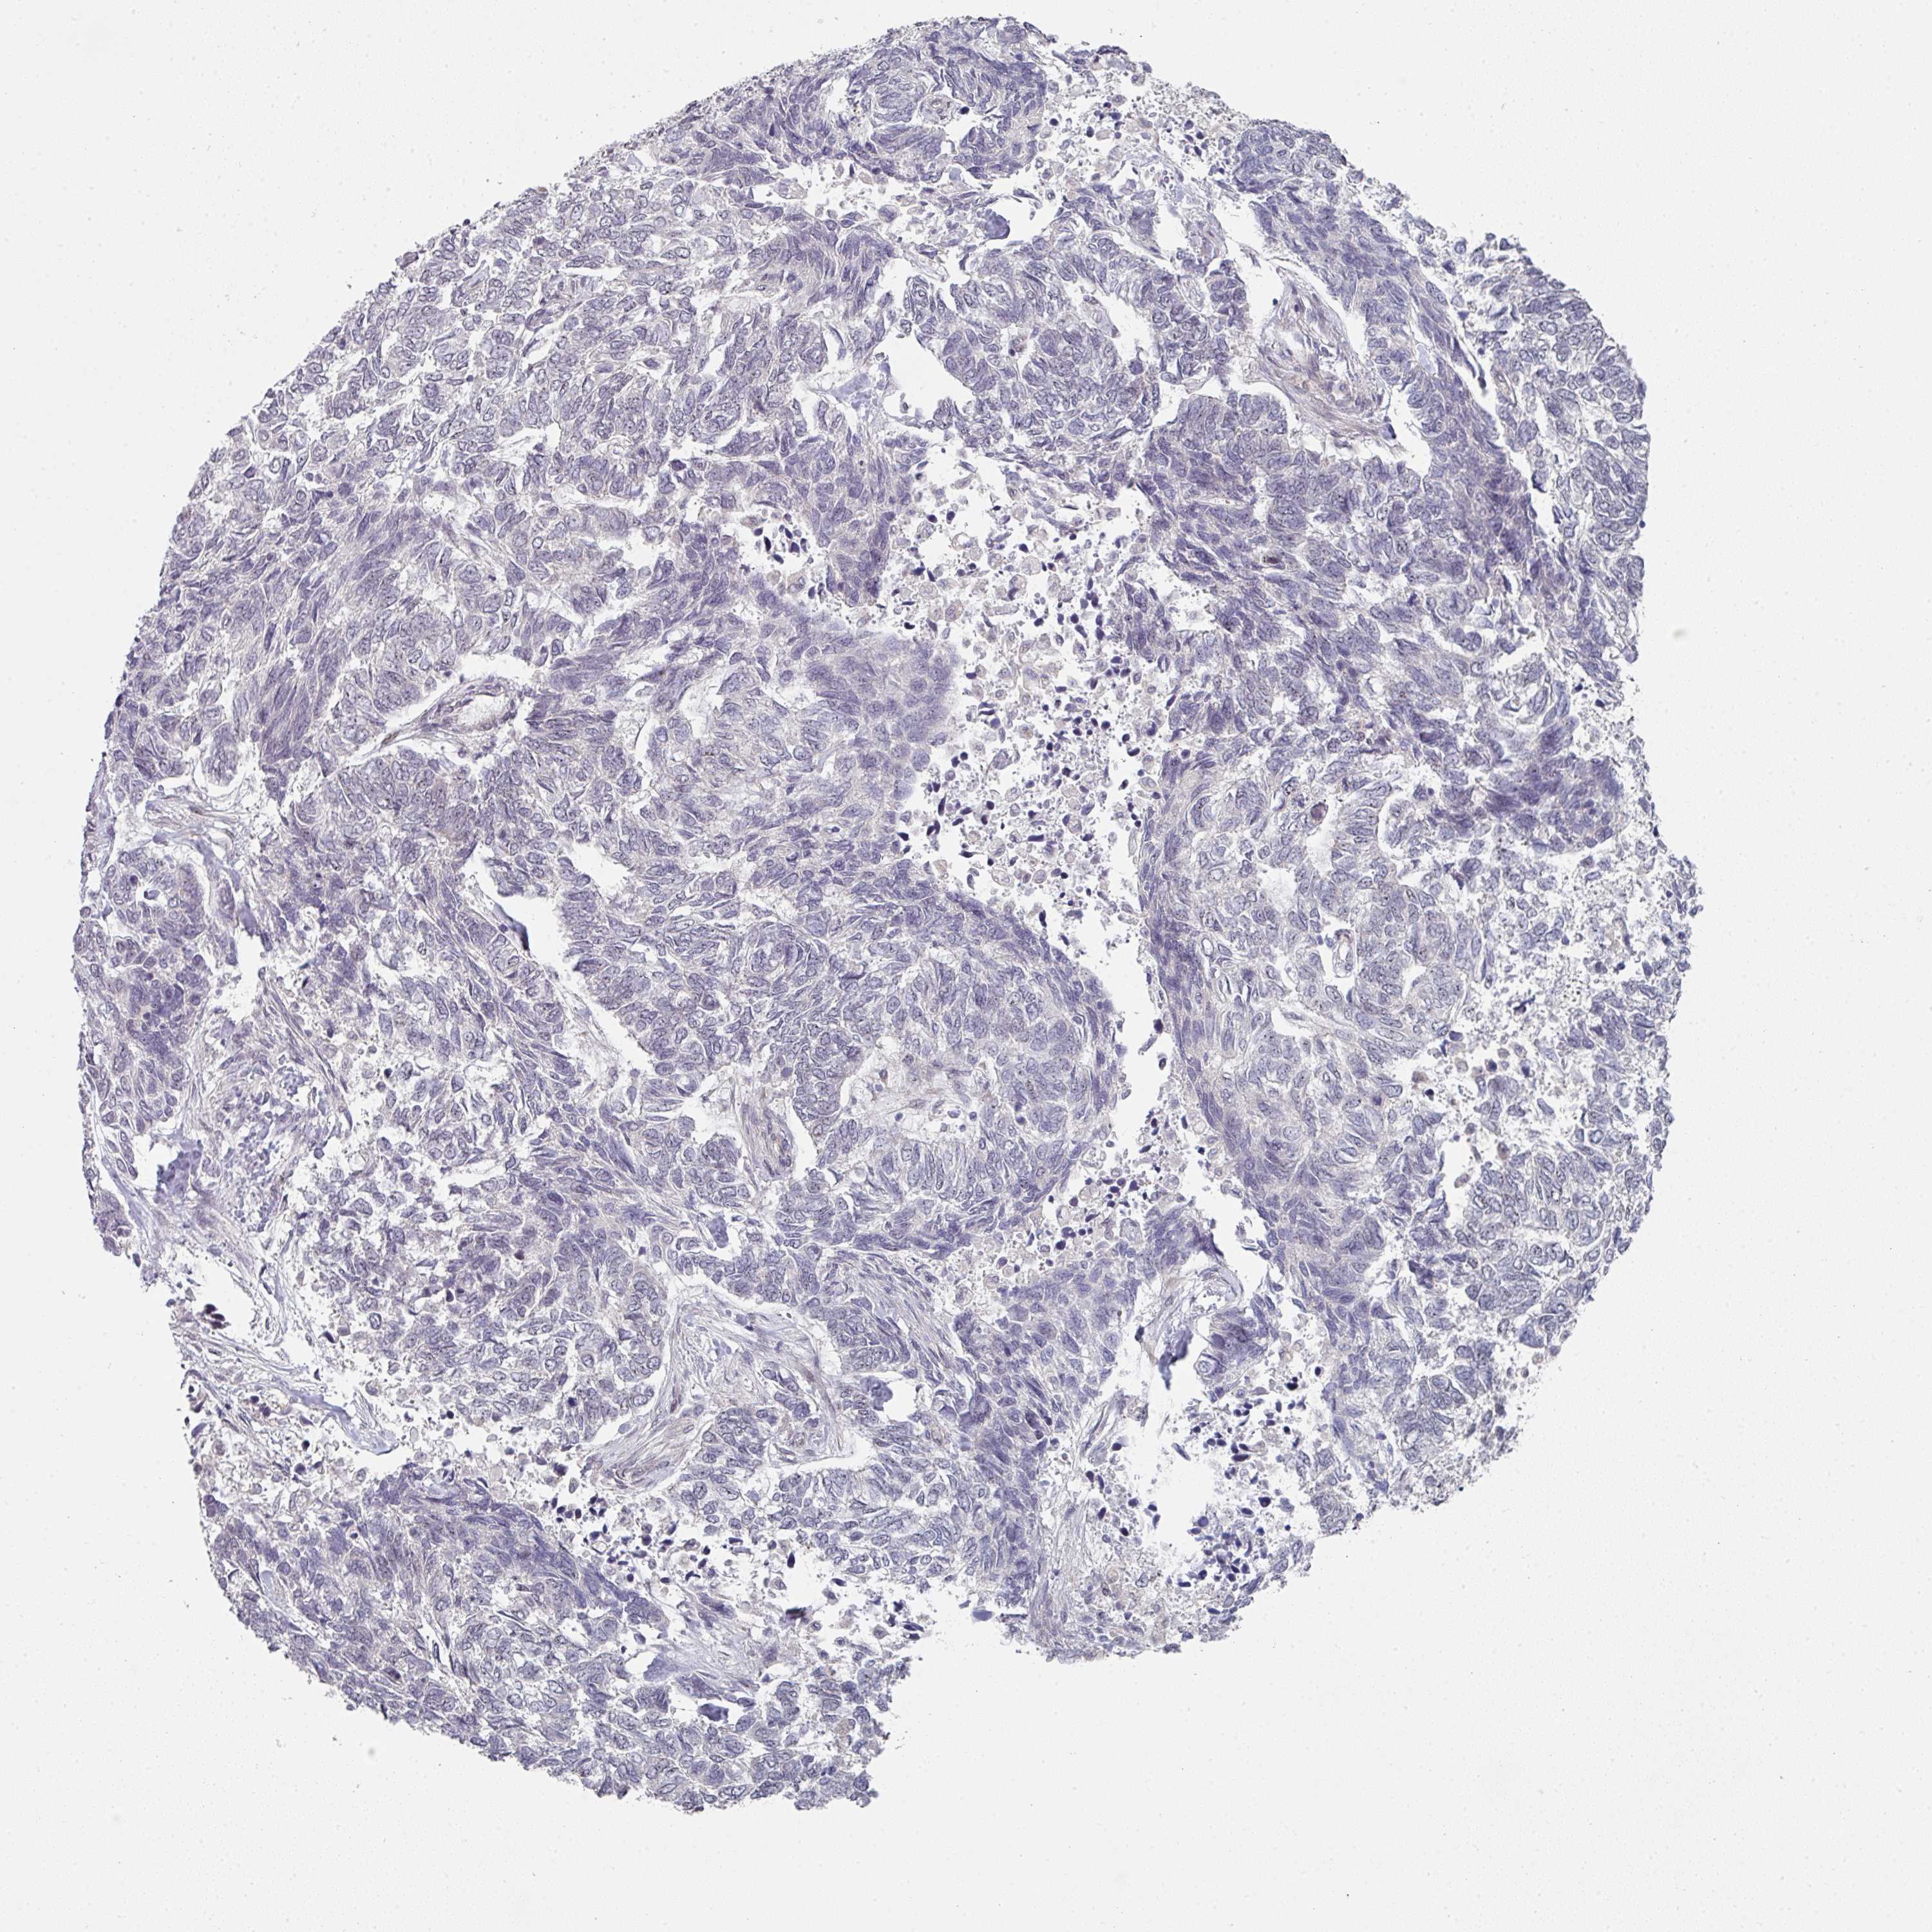

CANCER SKIN CANCER Show tissue menu

Basal cell and squamous cell cancer

SKIN CANCER - Protein expressioni

A mouse-over function shows sample information and annotation data. Click on an image to view it in a full screen mode. Samples can be filtered based on level of antibody staining by selecting one or several of the following categories: high, medium, low and not detected. The assay and annotation is described here.

Each image is clickable and will lead to virtual microscopy that enables deeper exploration of all samples and also displays staining intensity scores, fraction scores and subcellular localization as well as patient and tissue information for each sample.

Antibody HPA053894

Staining

High

Medium

Low

Not detected

Intensity

Strong

Moderate

Weak

Negative

Quantity

>75%

75%-25%

<25%

None

Location

Nuclear

Cytoplasmic/membranous

Cytoplasmic/membranous,nuclear

Basal cell carcinoma

Squamous cell carcinoma, NOS